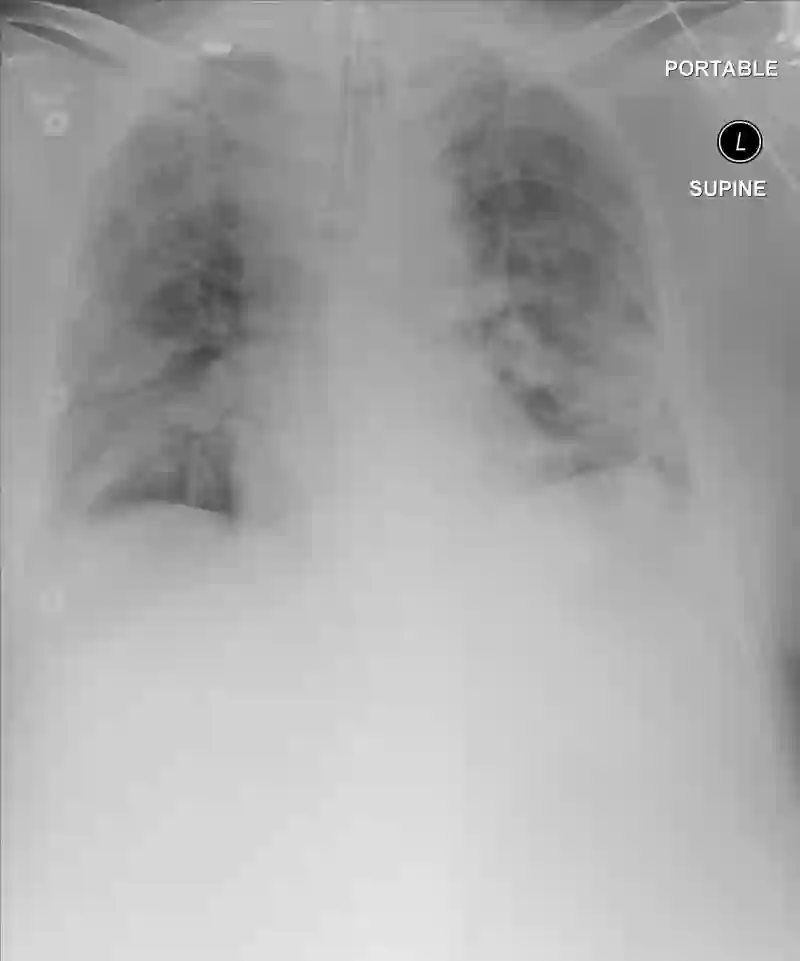

Chest radiography has been a recommended procedure for patient triaging and resource management in intensive care units (ICUs) throughout the COVID-19 pandemic. The machine learning efforts to augment this workflow have been long challenged due to deficiencies in reporting, model evaluation, and failure mode analysis. To address some of those shortcomings, we model radiological features with a human-interpretable class hierarchy that aligns with the radiological decision process. Also, we propose the use of a data-driven error analysis methodology to uncover the blind spots of our model, providing further transparency on its clinical utility. For example, our experiments show that model failures highly correlate with ICU imaging conditions and with the inherent difficulty in distinguishing certain types of radiological features. Also, our hierarchical interpretation and analysis facilitates the comparison with respect to radiologists' findings and inter-variability, which in return helps us to better assess the clinical applicability of models.